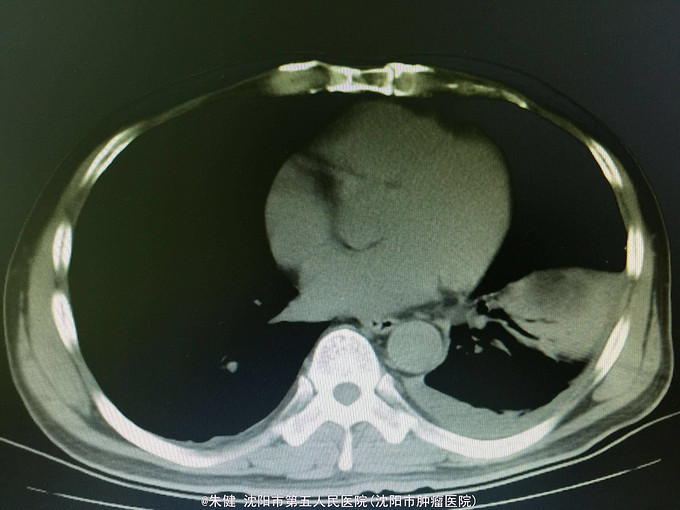

一般状态可,腹部平坦,未见肠形及蠕动波,剑突下及左侧上腹部压痛,轻度肌紧张,未及包块,无移动性浊音,肠音正常,肾区无扣痛。 辅助检查:血常规:白细胞13.6*10^9/L,中性83.3/L;尿淀粉酶:214U/L,上腹部CT:左侧胸腔积液,左肺下叶可见斑片及索条状影;胆囊增大,胆道内未及结石影;胰腺形态及密度正常,胰腺尾部周围可见索条状影及积液影。

诊断:急性胰腺炎 处理:给予禁食、补液、抗炎及抑肽酶治疗,病情逐渐好转,一周后出院。